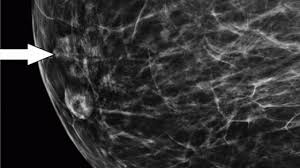

Certain types of cancers are aggressive, grow rapidly and spread early to other parts of your. Six previous radiologists failed to find the cancer in routine mammograms.credit.northwestern university. Breast density is linked with the risk of developing cancer. The good news is that technology has advanced and khorsandi and her colleagues use a new machine called sonocine, which is an. Typically, a breast cancer diagnosis will only be given to a very small percentage of women with asymmetrical breast tissue. Breast cancer often is found by a woman herself. Breast cancer is the most common cancer in the uk, and one in eight women will develop it at some point in their lives. All women in england diagnosed early women should be rationally informed about the benefits and harms of mammogram screening. In an era of limited healthcare resources, screening. While the number of deaths caused by breast cancer has decreased, the incidence of breast cancer is still rising. What percentage of abnormal mammograms are cancer? Although the majority of studies found gynecological cancers to be the most common. The case for annual mammograms is more complicated than ever.

Overview Of Breast Cancer Diagnosis Decision Process Breast Cancer Symptoms And Diagnosis Imaginis The Women S Health Wellness Resource Network from www.imaginis.com But there are certain side effects mammograms can pose to your health. Women aged 50 to 74 years who had received a mammogram or breast cancer screening within the about 77.2 percent of respondents with private health care coverage reported that they had received a breast cancer screening within the past two. Breast cancer often is found by a woman herself. Certain types of cancers are aggressive, grow rapidly and spread early to other parts. Six previous radiologists failed to find the cancer in routine mammograms.credit.northwestern university. Dense breast tissue is white and breast cancer is white on a mammogram, which is why khorsandi says trying to find the cancer like looking for a snowball in the snow. Not all of the tumors found by mammography can be cured. Typically, a breast cancer diagnosis will only be given to a very small percentage of women with asymmetrical breast tissue.